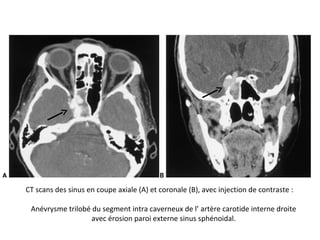

CT scans des sinus en coupe axiale (A) et coronale (B), avec injection de contraste :

Anévrysme trilobé du segment intra caverneux de l’ artère carotide interne droite

avec érosion paroi externe sinus sphénoidal.